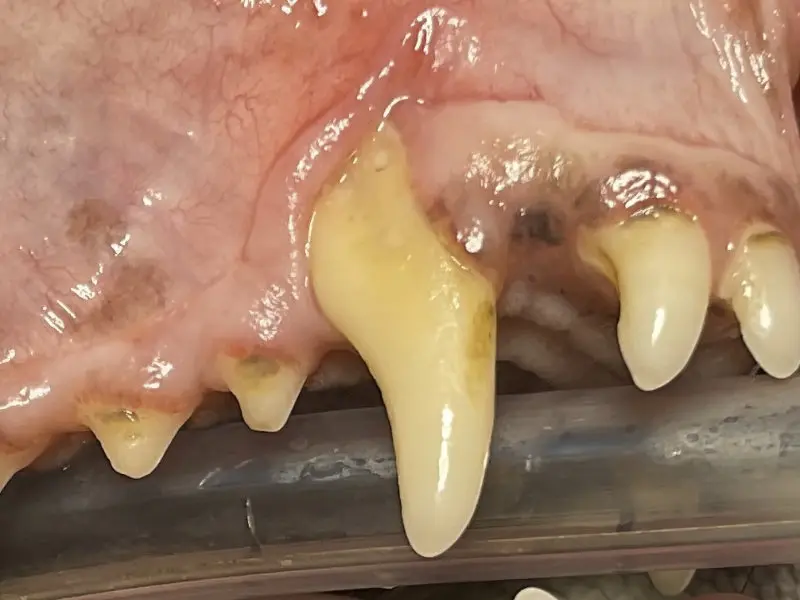

By three years old most dogs and cats have evidence of periodontal disease, an infection caused by bacteria in the tissues surrounding and supporting the teeth. The most prevalent sign of PD is bad breath.

Periodontal disease is a painful infection that, if left untreated, will progress to bone loss, mobile teeth, and eventually tooth loss. PD can lead to larger, more severe issues, such as jaw fracture due to bone loss and bone infection.

Periodontal disease is not always apparent during an initial consultation because it mainly occurs under the gum line. A complete exam is conducted under general anesthesia to evaluate each tooth for periodontal disease and the tissues that surround it.

Generally, this is determined by probing, charting, and radiographs. Without these diagnosis tools, these painful problems will remain undetected.